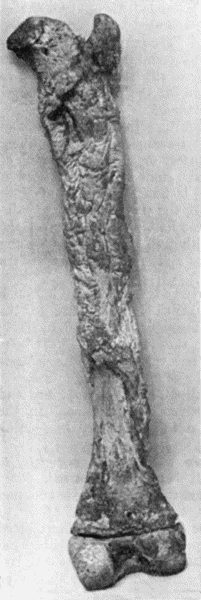

Another modification is to raise the flap but leave it connected at both ends like the piers of a bridge; this method is well suited to defects of skin on the dorsum of the fingers, hand and forearm, the bridge of skin is raised from the abdominal wall and the hand is passed beneath it and securely fixed in position; after an interval of 14 to 21 days, when the flap is assured of its blood supply, the piers of the bridge are divided (Fig. 1). With undermining it is usually easy to bring the edges of the gap in the abdominal wall together, even in children; the skin flap on the dorsum of the hand appears rather thick and prominent—almost like the pad of a boxing-glove—for some time, but the restoration of function in the capacity to flex the fingers is gratifying in the extreme.

Fig. 1.—Ulcer of back of Hand covered by flap of skin raised from anterior abdominal wall. The lateral edges of the flap are divided after the graft has adhered.